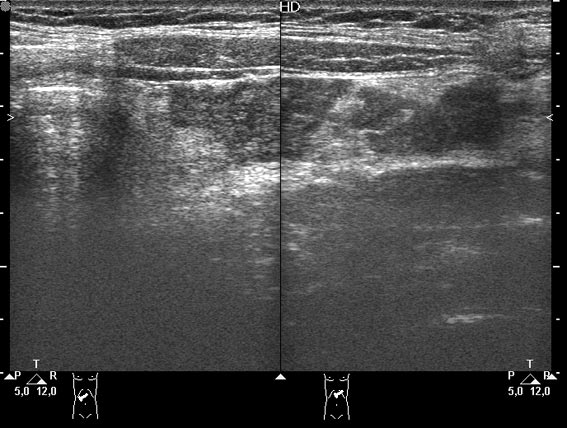

Девочка-подросток поступила в приемное отделение с жалобами на боли в эпигастральной области. На животе - рубец после срединной лапоротомии - полгода назад оперирована по поводу травмы и разрыва селезенки, со слов мамы - выполнена спленэктомия.

При УЗИ в эпигастральной области обнаружилось такое образование.

Да, действительно, это аутотрансплантат ткани селезенки в большой сальник.